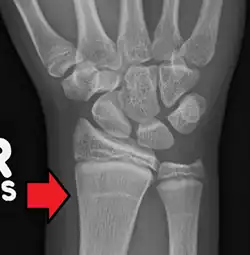

Harris-Linien im Röntgenbild des Radius

Harris-Linien sind Linien höherer Knochendichte, die im Röntgenbild erkennbar sind. Sie verlaufen parallel zur Epiphysenfuge in der Metaphyse langer Knochen – insbesondere des Schienbeines (Tibia) – und sind ein Zeichen für eine kurzzeitige Veränderung im Längenwachstum der Knochen. Im englischen Sprachraum sind die Bezeichnungen Harris lines, growth arrest lines, recovery lines, stress lines, Park-Harris growth arrest lines oder auch Park lines im Gebrauch. Der Name geht auf den Erstbeschreiber, den walisischen Anatomen Henry Albert Harris, zurück bzw. auf Edwards Albert Park (1877–1969).